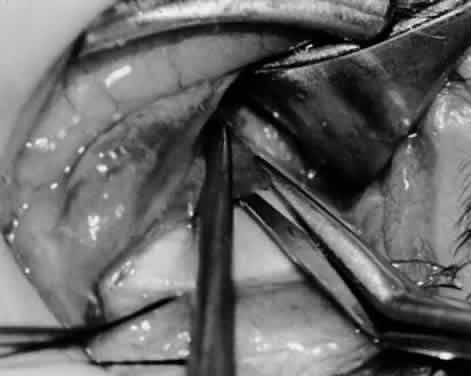

and extirpation, and anterior transposition.10 MYOTOMY An inferior oblique myotomy usually is performed between the nerve to the inferior oblique muscle and the insertion of the muscle. After the muscle is crushed with one or two hemostats, transverse surgical sectioning of the muscle is performed. Suture ligatures or cautery may be used for hemostasis. If the inferior oblique muscle is isolated properly, this procedure is not complicated and is performed rapidly. The severed ends of the inferior oblique muscle tend to reunite, however, and the preoperative state may be resumed within several months.2,10 MYECTOMY An inferior oblique myectomy includes removal of a section of the muscle to reduce the tendency of the myotomized ends to reunite. Two hemostats are used, as with the myotomy, except that a space of 5 mm or more is maintained between the hemostats, so that the segment of muscle between the hemostats can be removed. Cautery, ligature, or both are used for hemostasis. This procedure offers the same advantages as the myectomy but the cut ends still tend to reunite.10 Parks2,11 performed a controlled prospective study comparing the various methods of weakening the inferior oblique muscle. The study included 638 consecutive patients who had a minimum follow-up of 2 years. Parks performed 19 myectomies at the origin of the inferior oblique, 86 myectomies at the insertion, 89 disinsertions, and 444 recessions of inferior oblique muscles. The overaction of the inferior oblique muscle returned in 79% of the 19 eyes that underwent a myectomy at the origin. Because the recurrence rate is high and the procedure is difficult to perform, this procedure is no longer performed. Myectomy at the insertion produced a 37% return on overaction, also causing that procedure to be abandoned by Parks. Many authors, however, still prefer this procedure and advocate its use. Dyer1 reported a 91% success rate in reducing the hypertropia to 10 diopters or less, and Davis and coworkers12 reported a 93% success rate. DISINSERTION Disinsertion occurs at the scleral attachment of the inferior oblique muscle. Assuming proper exposure of the inferior oblique, this procedure is performed rapidly. The reattachment rate of the inferior oblique tendon is not predictable, however. It has a tendency to attach at or near the original insertion site or to the inferior border of the lateral rectus muscle.10 Parks2,11 found a 53% rate of return of overaction, worse than that for the myectomy procedure at the insertion end. Jones and associates,13 however, reported a success rate of 88% with inferior oblique disinsertion. RECESSION In comparing the various weakening procedures, Parks2,11 concluded that the recession procedure was superior (Figs. 1–20). The major advantage of the recession is that it allows the weakening procedure to be titrated according to the severity of the overaction. For 1+ overaction, the inferior oblique muscle is recessed 6 mm; for 2+ overaction, 10 mm; and for 3+ overaction, 14 mm, which is the maximum recession. A double-armed 6-0 synthetic suture, such as polyglactin (Vicryl [J-562]*) with a half-circle spatula needle (S-28*), is placed within the insertion of the inferior oblique with a locked bite at the anterior and posterior border (see Fig. 11). With an Aebli scissor, the muscle is sectioned from the globe (see Fig. 12) and recessed 6 mm by placing the anterior suture 4 mm lateral to the lateral insertion of the inferior rectus muscle and the posterior suture 3 mm more laterally. The 10-mm recession (see Figs. 15, 17, 18, 20) requires placement of the anterior suture 2 mm temporal and 3 mm posterior to the temporal insertion of the inferior rectus muscle, with the posterior suture placed 3 mm more posteriorly. The 14-mm recession (see Figs. 14, 16, 19, 20) requires placement of the anterior and posterior sutures parallel to the inferior-temporal vortex vein, which usually is found 8 mm posterior to the temporal insertion of the inferior rectus muscle.

Ethicon, Somerville, NJ. Ethicon, Somerville, NJ. Because the inferior oblique muscle inserts near the macula, there may be concern about penetration of the macula with a preplaced suture, which can cause macula hemorrhage, visual impairment, or visual loss. An alternative is to place a hemostat near the insertion of the inferior oblique muscle and then section the muscle from the globe with the Aebli scissor. The 6-0 Vicryl suture can be placed within the muscle, which is grasped by the hemostat and a locked bite placed at the anterior and posterior borders of the muscle, before the muscle is reattached to the sclera at the intended position. The technique of removing the inferior oblique muscle with the hemostat is part of the denervation and extirpation procedure. The disadvantage of the recession procedure is the difficulty involved in performing the procedure within a small operative field with limited visibility, compared with the myectomy or disinsertion. With proper illumination, however, such as the surgeon wearing the operating headlight and exposure with the Desmarres or Conway lid retractor, the inferior oblique insertion readily can be seen for placement of sutures and separation of the inferior oblique from the sclera. Parks2,11 found that 15% of patients had a return of overaction with the recession procedure, compared with 79% with myectomy at the origin, 53% with disinsertion, and 37% with myectomy at the insertion. Short-term follow-up is not helpful with oblique muscle surgery because inferior oblique overaction can return gradually over 2 years.10 Therefore, long-term follow-up is necessary for proper evaluation of success. In a more recent report, Wilson and Parks14 found a 25% recurrence rate of inferior oblique overaction after surgery, with an average follow-up of 3 years. Only 6% of patients required repeat inferior oblique surgery, however. DENERVATION Gonzalez15 first described denervation of the inferior oblique muscle as a weakening procedure but also reported the return of overaction within the first postoperative year.16,17 The nerve to the inferior oblique is attached tightly to the posterior belly of the inferior oblique muscle, lateral to the inferior rectus muscle border. At this site is a fusiform enlargement of the belly. After the nerve is hooked posteriorly with a Stevens hook, cautery is used to sever the nerve and the accompanying artery and vein. The procedure of denervation is no longer used alone because of the likelihood of recurrence of the inferior oblique overaction but it is used as the foundation for the denervation and extirpation procedure. DENERVATION AND EXTIRPATION The denervation procedure (Figs. 21–32) allows the inferior oblique muscle to be released further into the operative field once the nerve has been sectioned (see Figs. 26 and 27). A 3-0 Vicryl suture ligature is placed around the inferior oblique muscle (see Fig. 28) as close to the Tenon's capsule penetration as possible. The inferior oblique is sectioned by cautery (see Fig. 29), just distal to the suture ligature. The cauterized stump is pushed through the opening in the Tenon's capsule (see Figs. 30 and 31) and a 6-0 or 7-0 Vicryl suture is used to close the opening, with either a running or a purse-string suture (see Fig. 32). The purse-string suture can be preplaced before the inferior oblique muscle is sectioned and closed after the muscle is sectioned. The advantage of the denervation and extirpation procedure is its ability to permanently correct 4+ overaction of the inferior oblique.10,18 In addition, it is the best operative procedure to eliminate recurring inferior oblique overaction after disinsertion, myectomy, or recession.10 Disadvantages include permanent underaction of the inferior oblique muscle in some patients. Pupil dilation can occur but the dilation usually is transient, clearing in 3 to 6 months.10,18